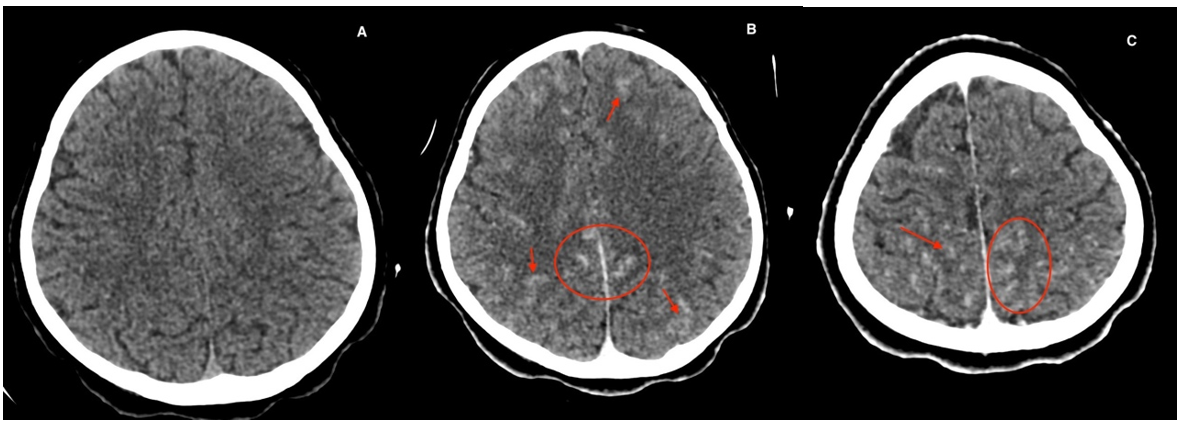

An electroencephalography (EEG) found a broad and slow background rhythm for the age of the delta band. No variation of the plot as a function of waking states. No paroxysmal anomaly. No seizure. A brain scan (Figure 1) showed a supra tentorial leptomengitis without abscess or brain complication.

Figure 1: Brain scan performed without (a) and after injection (b and c) of iodized product, showing a bilateral gyriform contrast enhancement (red arrows and circles) in favor of supratentorial leptomeningitis without abscess or encephalic complication.